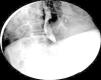

Se realizó una SEGD identificándose en el tercio inferior del esófago, un defecto de llenado redondeado localizado, el cual no condicionaba obstrucción al paso del medio contraste (fig. 2).